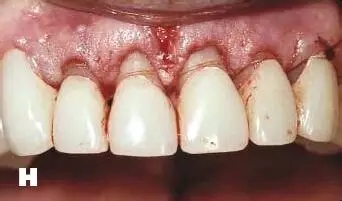

牙周炎發(fā)展到一定階段時(shí),僅采用基礎(chǔ)治療難以取得較好療效,必須通過(guò)適時(shí)而合宜的手術(shù)治療挽救患牙,才能保持牙周組織健康,延長(zhǎng)患牙在口腔內(nèi)的壽命,維持牙列的完整性,促進(jìn)全身健康。其手段包括齦下刮治、根面平整、牙周翻瓣術(shù)、牙齦切除術(shù)、牙周夾板固定術(shù)等。

1、美容手術(shù):針對(duì)牙齦增生、影響美觀效果的患者,進(jìn)行牙齦的美容切除手術(shù),修整牙齦的形態(tài),恢復(fù)美容效果。

2、牙冠延長(zhǎng)術(shù):在口腔修復(fù)治療中,一些患者的牙根條件略差,直接修復(fù)無(wú)法完成,需要通過(guò)牙周手術(shù)延長(zhǎng)牙冠,創(chuàng)造修復(fù)條件。